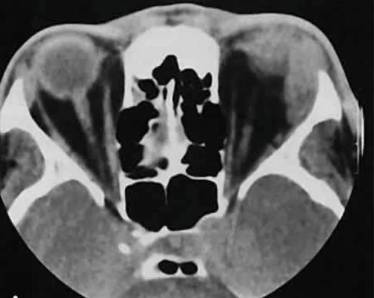

Также доктор оценивает температуру тела и общее состояние пациента. В случае выявления острых хрипов в бронхах при тугом дыхании может потребоваться флюорография. Когда шею продуло, может потребоваться УЗИ, которое позволит выявить наличие воспалительного процесса мышечных волокон.

2. УЗИ мышц – помогает определить степень выраженности воспалительного процесса в шее.